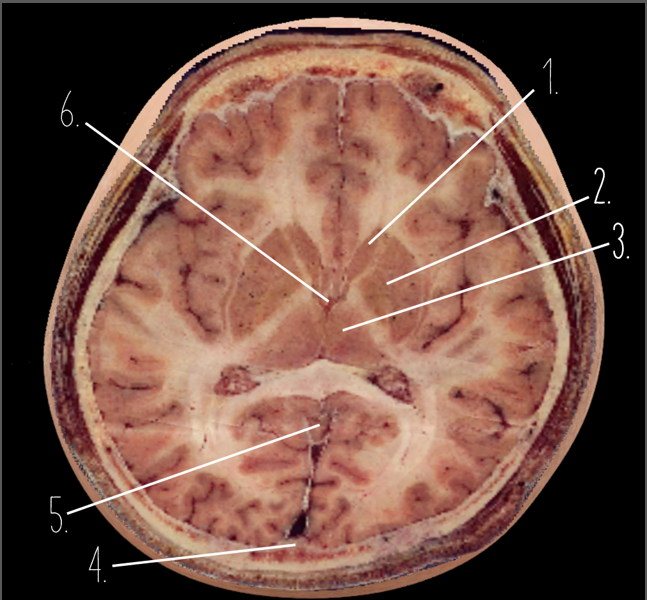

1

Frontal Bone

2

Frontal Lobe

3?

Falx Cerebri

4?

Gray Matter

5?

White Matter

6?

Sulcus